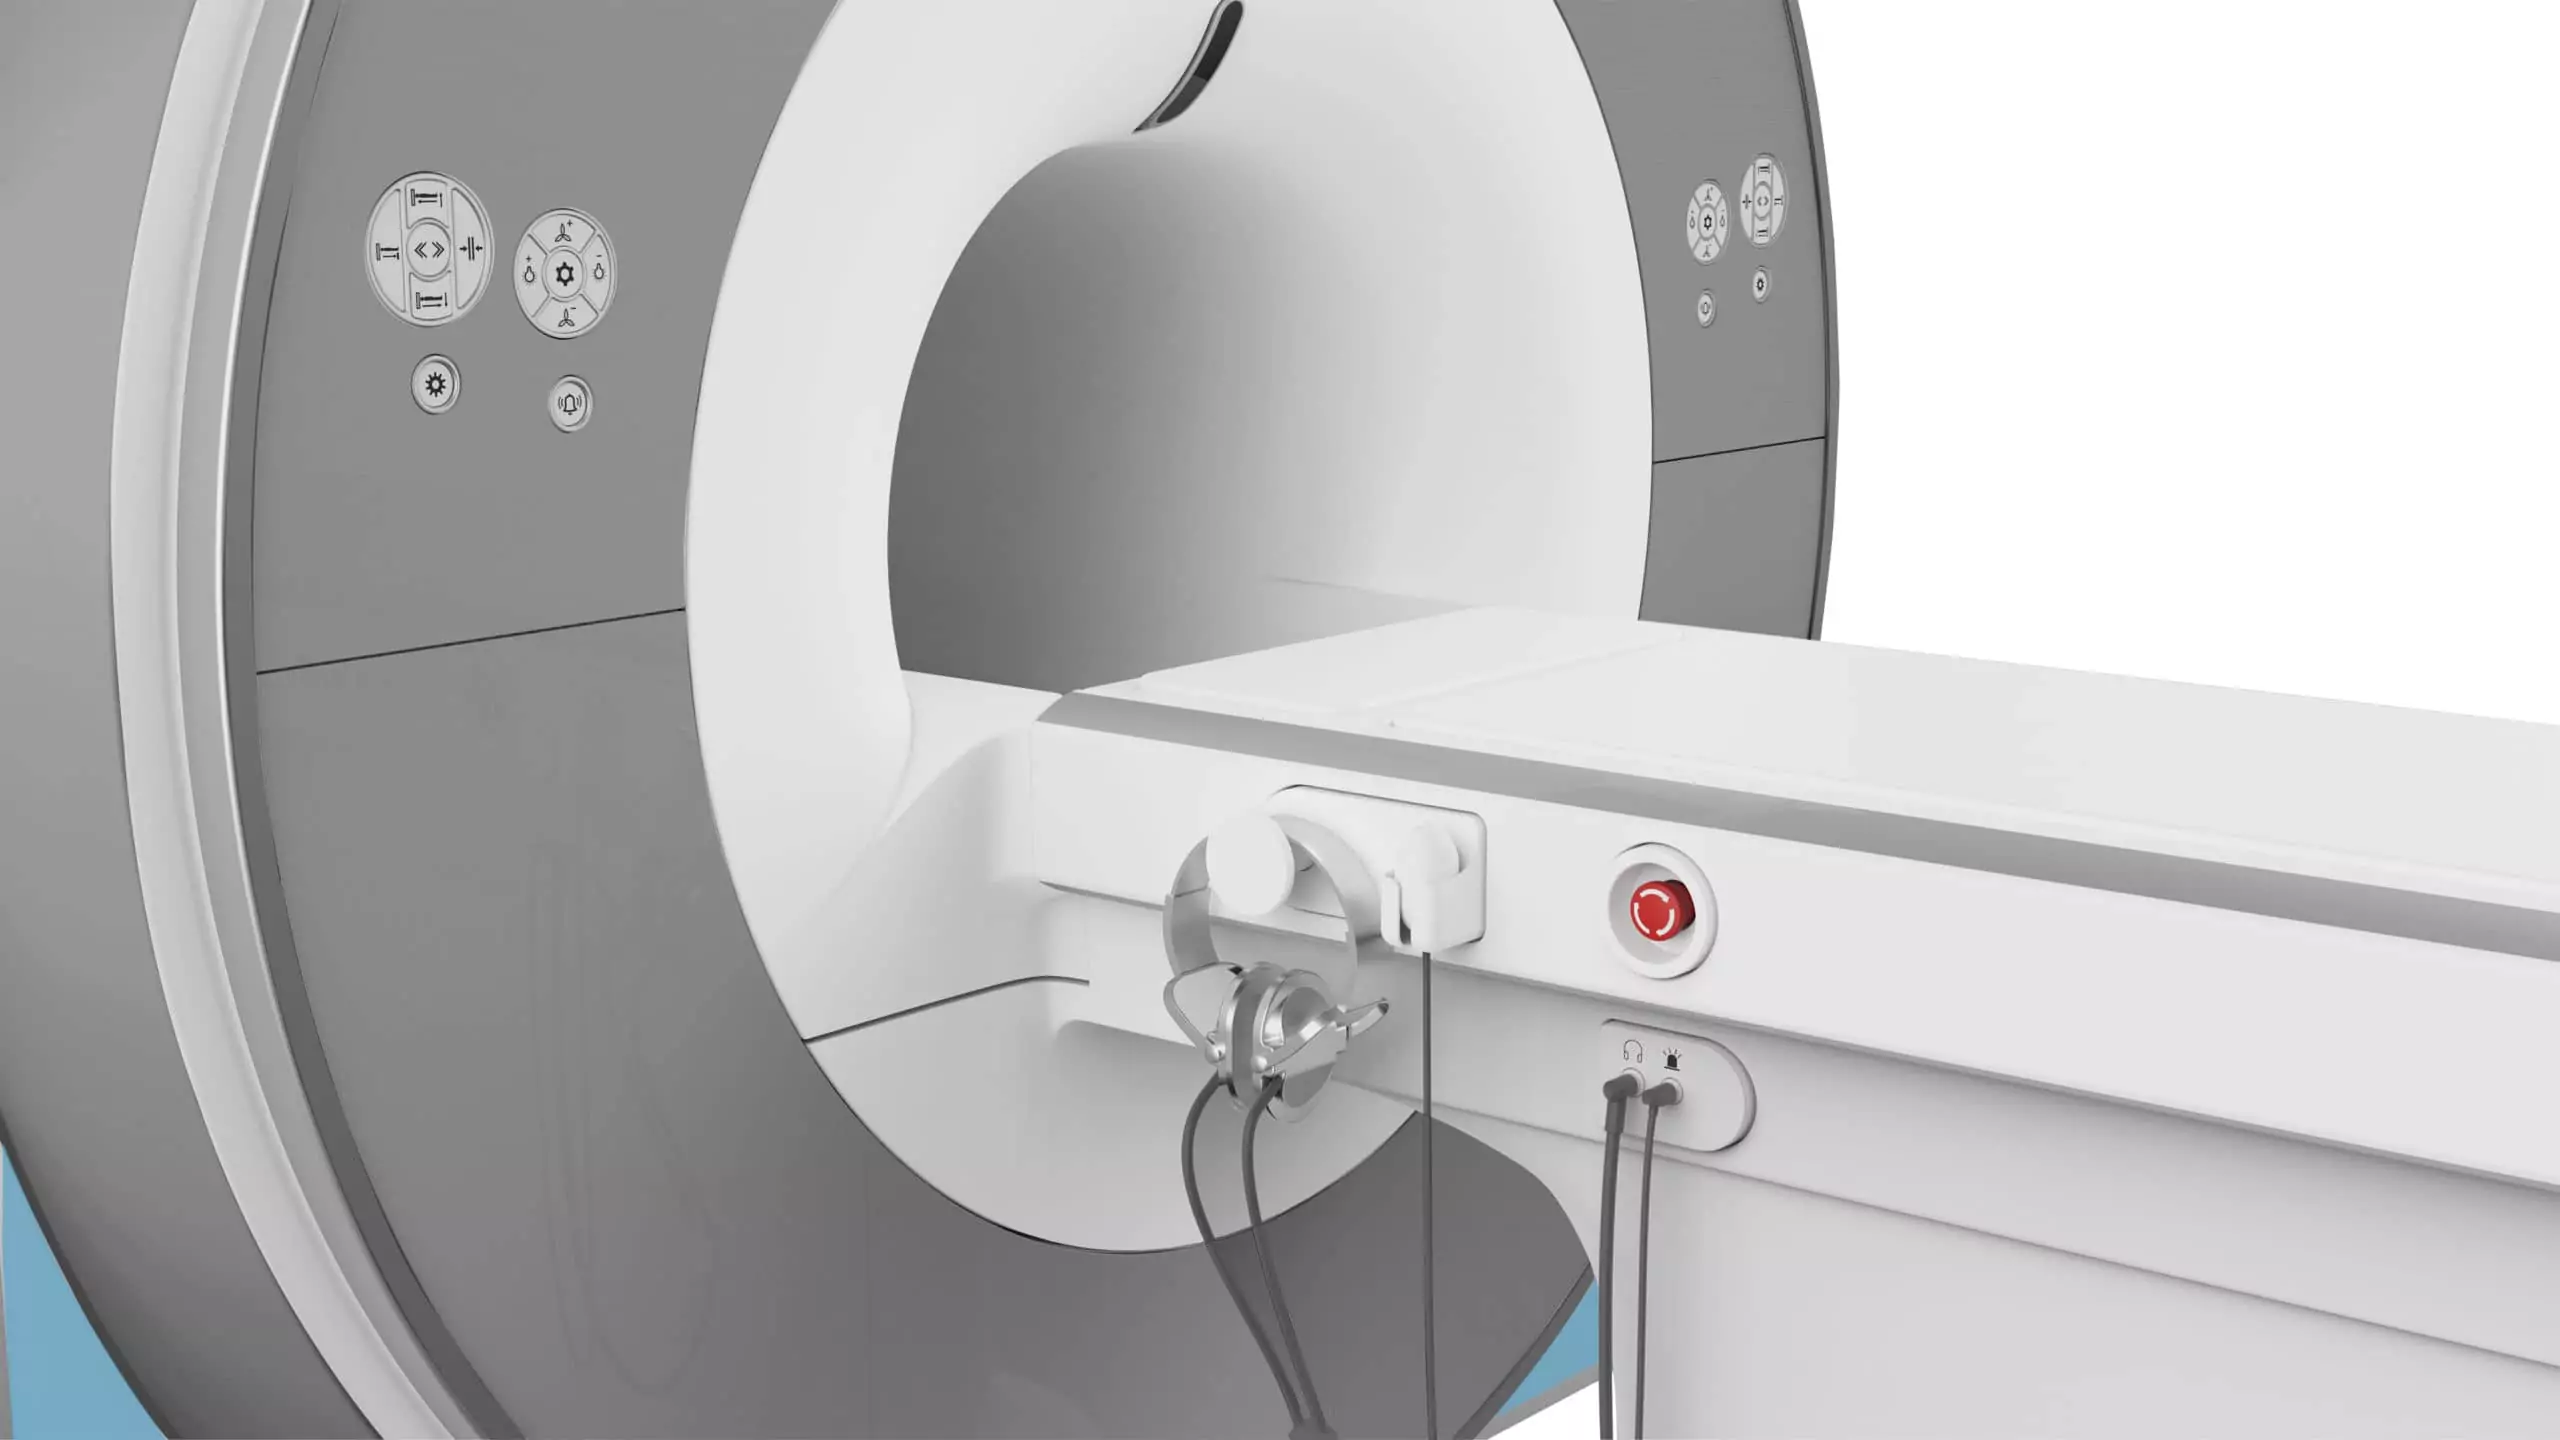

Marcom 1.5T

Marca: SternMed

Marcom 1.5T es un escáner superconductivo de resonancia magnética de nueva generación con una intensidad de campo de 1,5 Tesla con capacidad para realizar exploraciones de todo el cuerpo, como: el sistema nervioso, la columna, los tejidos blandos de las articulaciones, la cavidad pélvica y abdominal, etc.

El brillante diseño del imán crea un sistema compacto para minimizar el espacio necesario a 35 metros cuadrados.